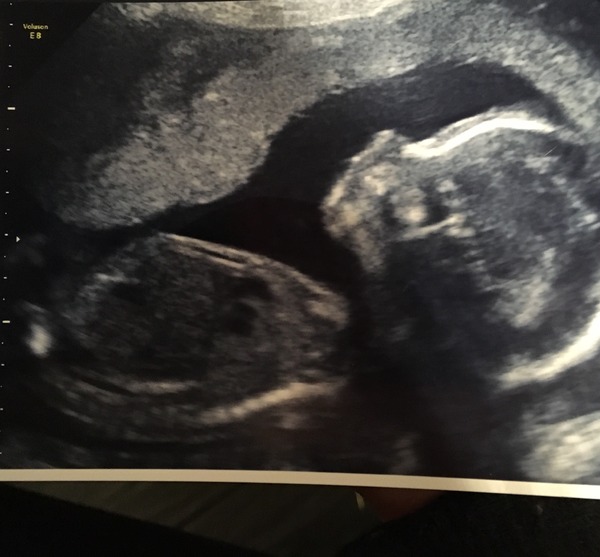

20 week scan went great! She is just beautiful and was amazing watching her moving around and listening to sonographer explain everything and be able to see such detail. Had to go to the bathroom and then move around a little to get her to move her arm which was blocking a full view of the heart at first but everything was perfect. SmileSmile

Woodsy, what a beautiful scan picture. Congrats! My 20 week scan is tomorrow and I am actually really looking forward to it. I was half sick with nerves at the 12 week one.

What a beautiful scan photo! So glad everything went well Smile your baby looks super cute, so clear Thanks